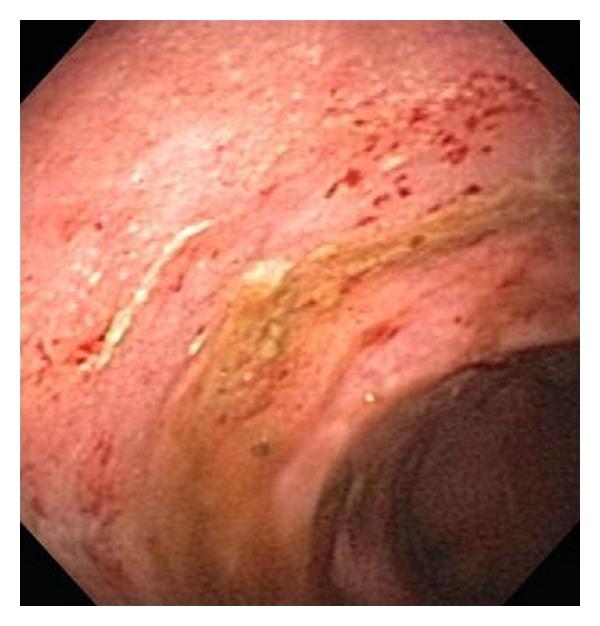

We report a case of ulcerative colitis (UC) and recurrent Clostridium difficile infection (CDI) where the patient was on immunomodulatory therapy and had successful CDI eradication after fecal transplantation. This is the first case report in the literature documenting successful C. difficile eradication in an immunosuppressed patient. We feel that fecal transplantation should be studied as a treatment option in these patients.

我们报告了一例溃疡性结肠炎(UC)合并复发性艰难梭菌感染(CDI)的病例,该患者正在接受免疫调节治疗,在粪便移植后艰难梭菌感染得以成功根除。这是文献中首例记录免疫抑制患者艰难梭菌感染成功根除的病例报告。我们认为粪便移植应作为这些患者的一种治疗选择进行研究。